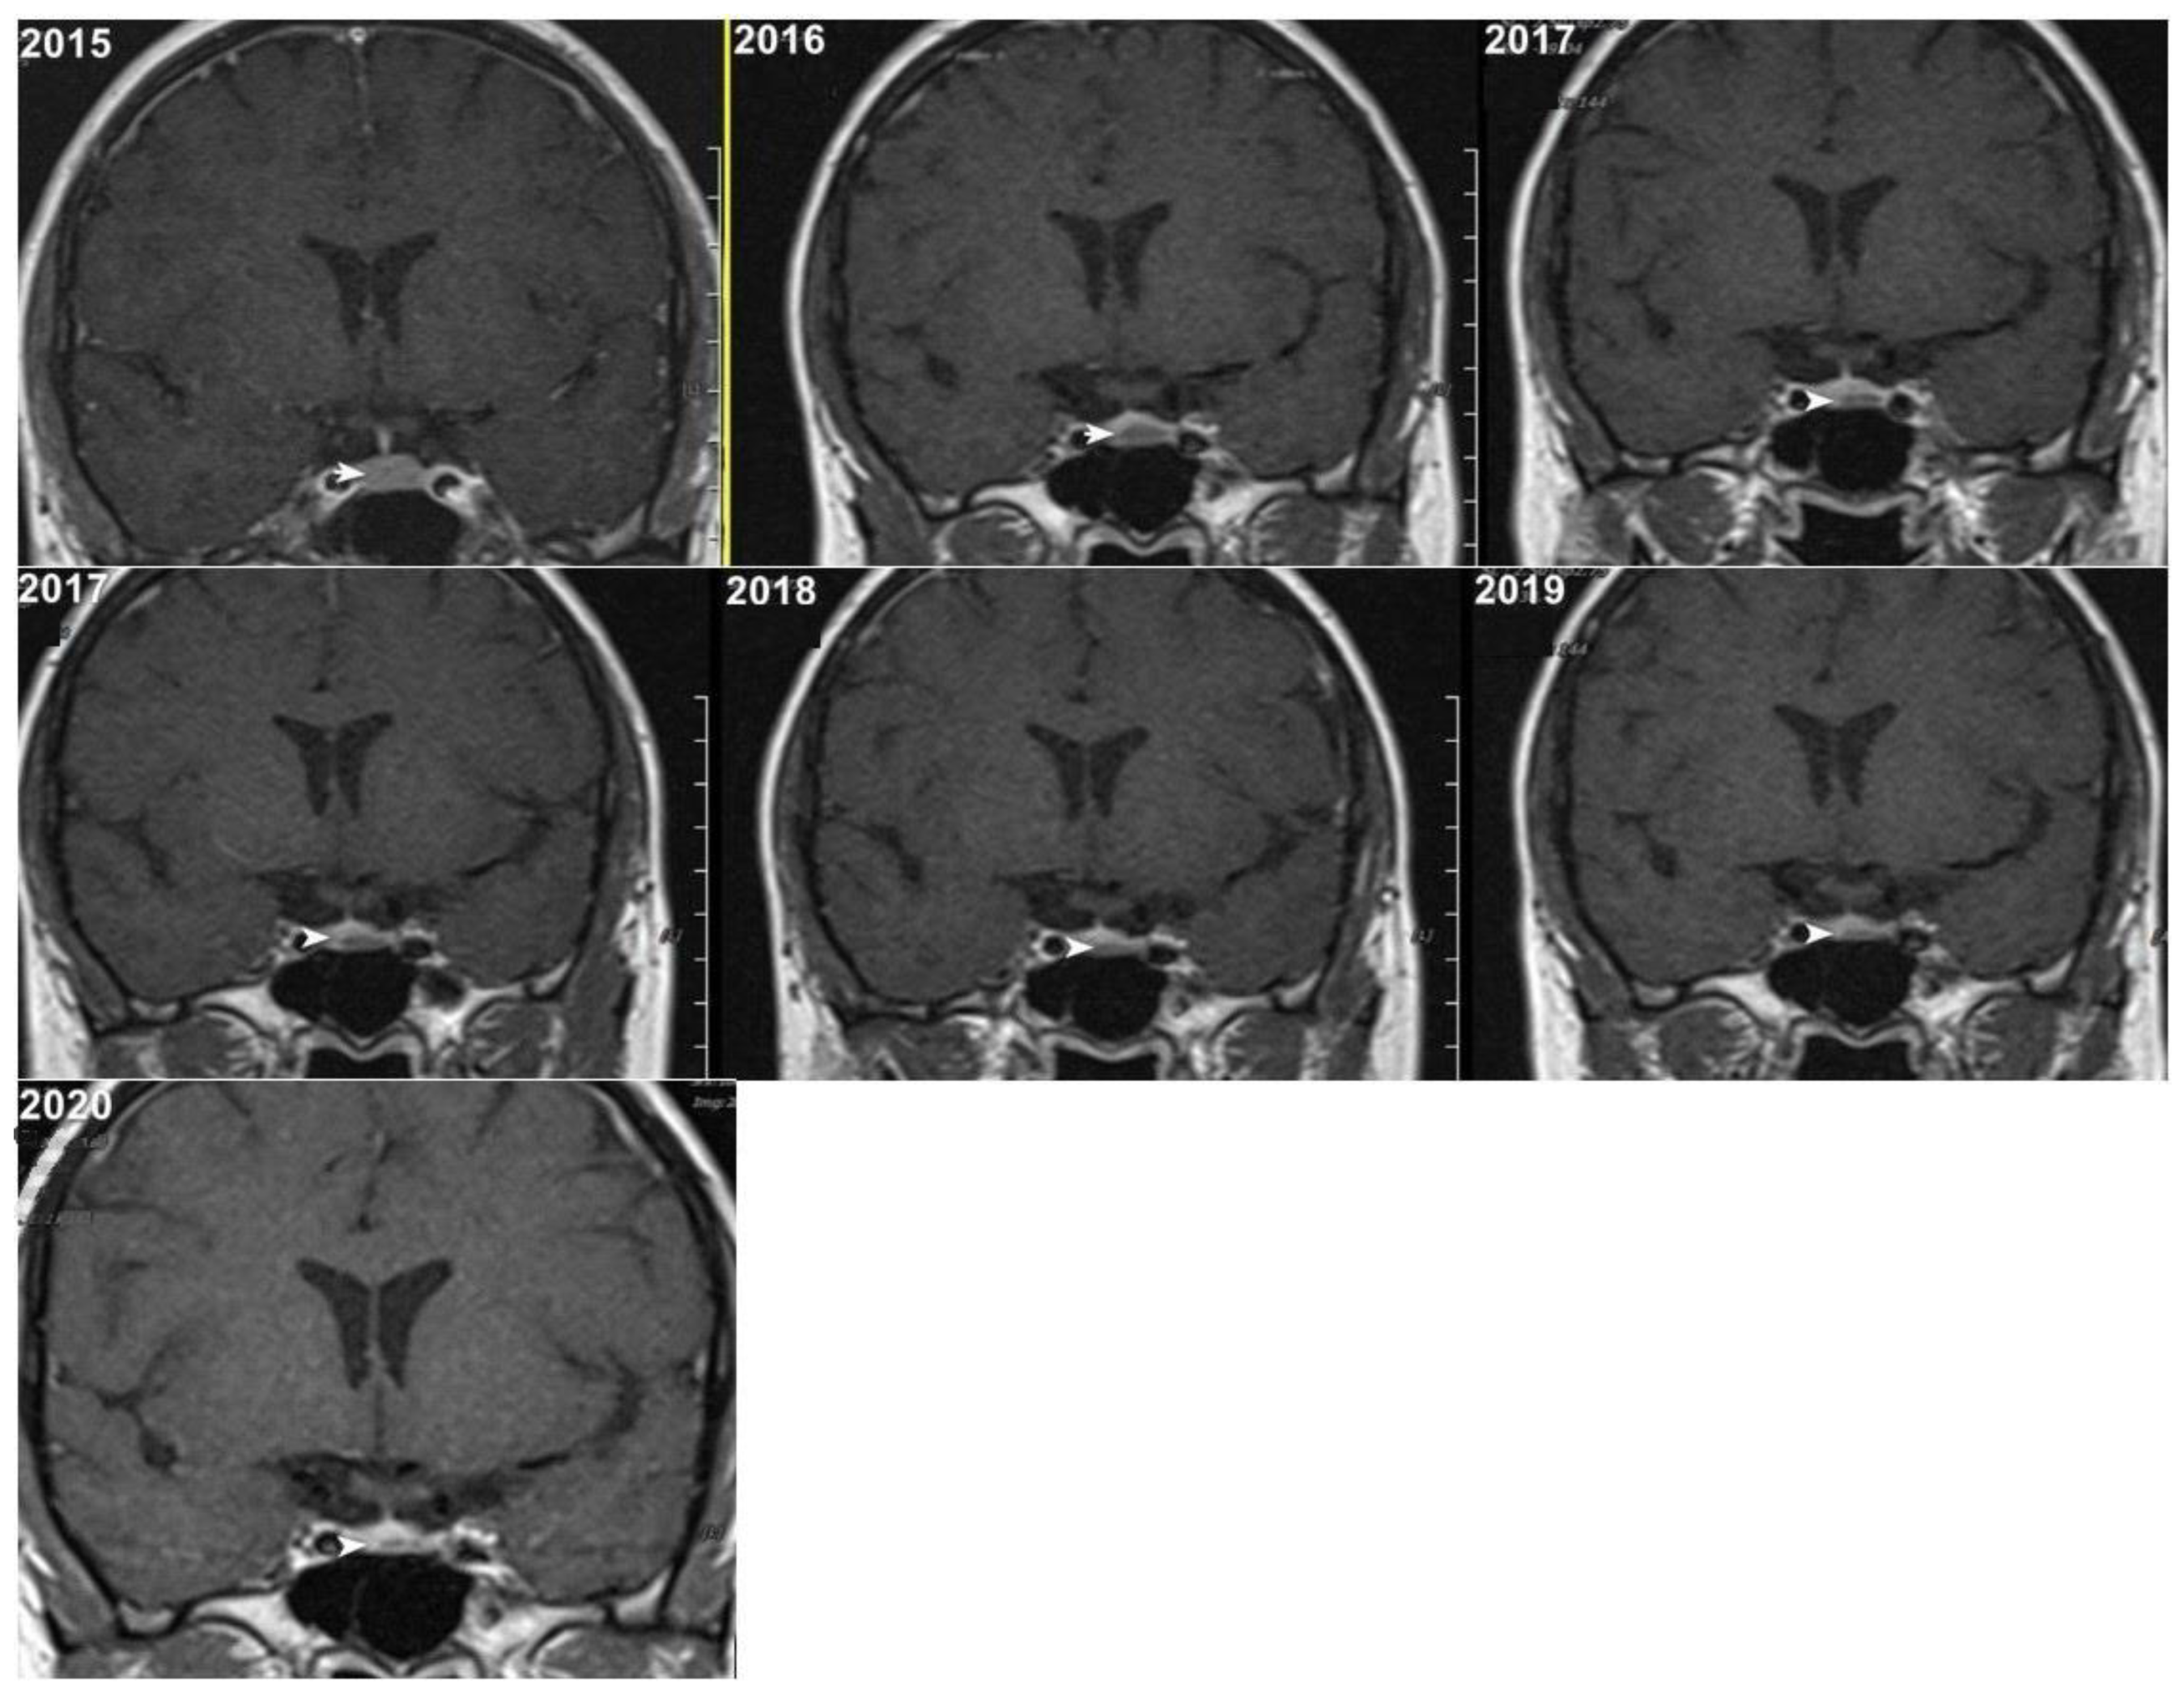

Although, the main cohort contained patients referred between 2020 and 2024, Figure 2, Figure 3 and Figure 4 shows a representative case with historical scans (2015–2020), retrieved from PACS, to demonstrate temporal stability. No evidence of recurrence of tumors in any of the nine who underwent resection of macroadenomas during this period was seen.

Figure 2.

Representative coronal images (2015–2020) of a stable microadenoma (arrows) of a 33 Y/O woman. The left upper image from 2015 is a delayed image, and the other six images are dynamic MRI follow-ups for this patient. In 2017, the patient had two follow-ups in the first and second half of the year. In the 5 years of follow-up, no size change can be seen.